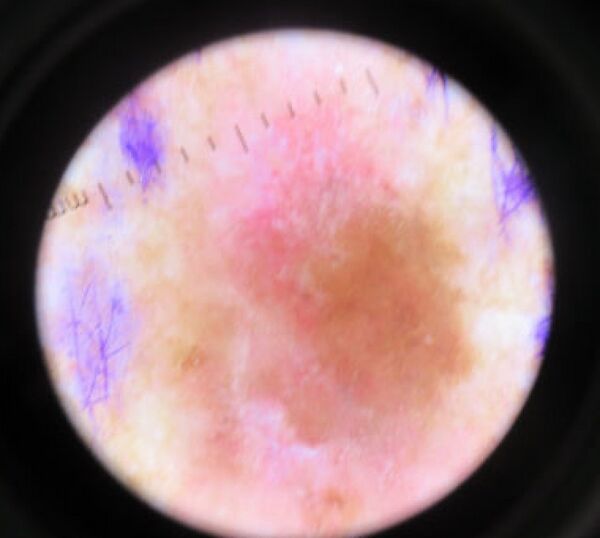

Диагноз

- Дерматоскопия — самая ранняя диагностика меланомы. Проводится как с помощью простой лупы, так и с помощью дерматоскопа (эпилюминисцентного микроскопа) делающего прозрачным роговой слой эпидермиса. При этом можно с высокой вероятностью определить, является ли невус опасным или нет на основании системы ABCDE, предложенную Friedman в 1985 году.

- A — asymmetry, асимметричность родинки

- B — border irregularity, неровный край

- C — color, неодинаковый цвет разных частей родинки

- D — diameter, диаметр родинки более 6 миллиметров

- E — evolving, изменчивость родинки

На сегодняшний день разработанные компьютерные системы микродермоскопии повышают уровень ранней диагностики меланомы с 60 % до 90 %, но часто только в экспериментальных условиях.